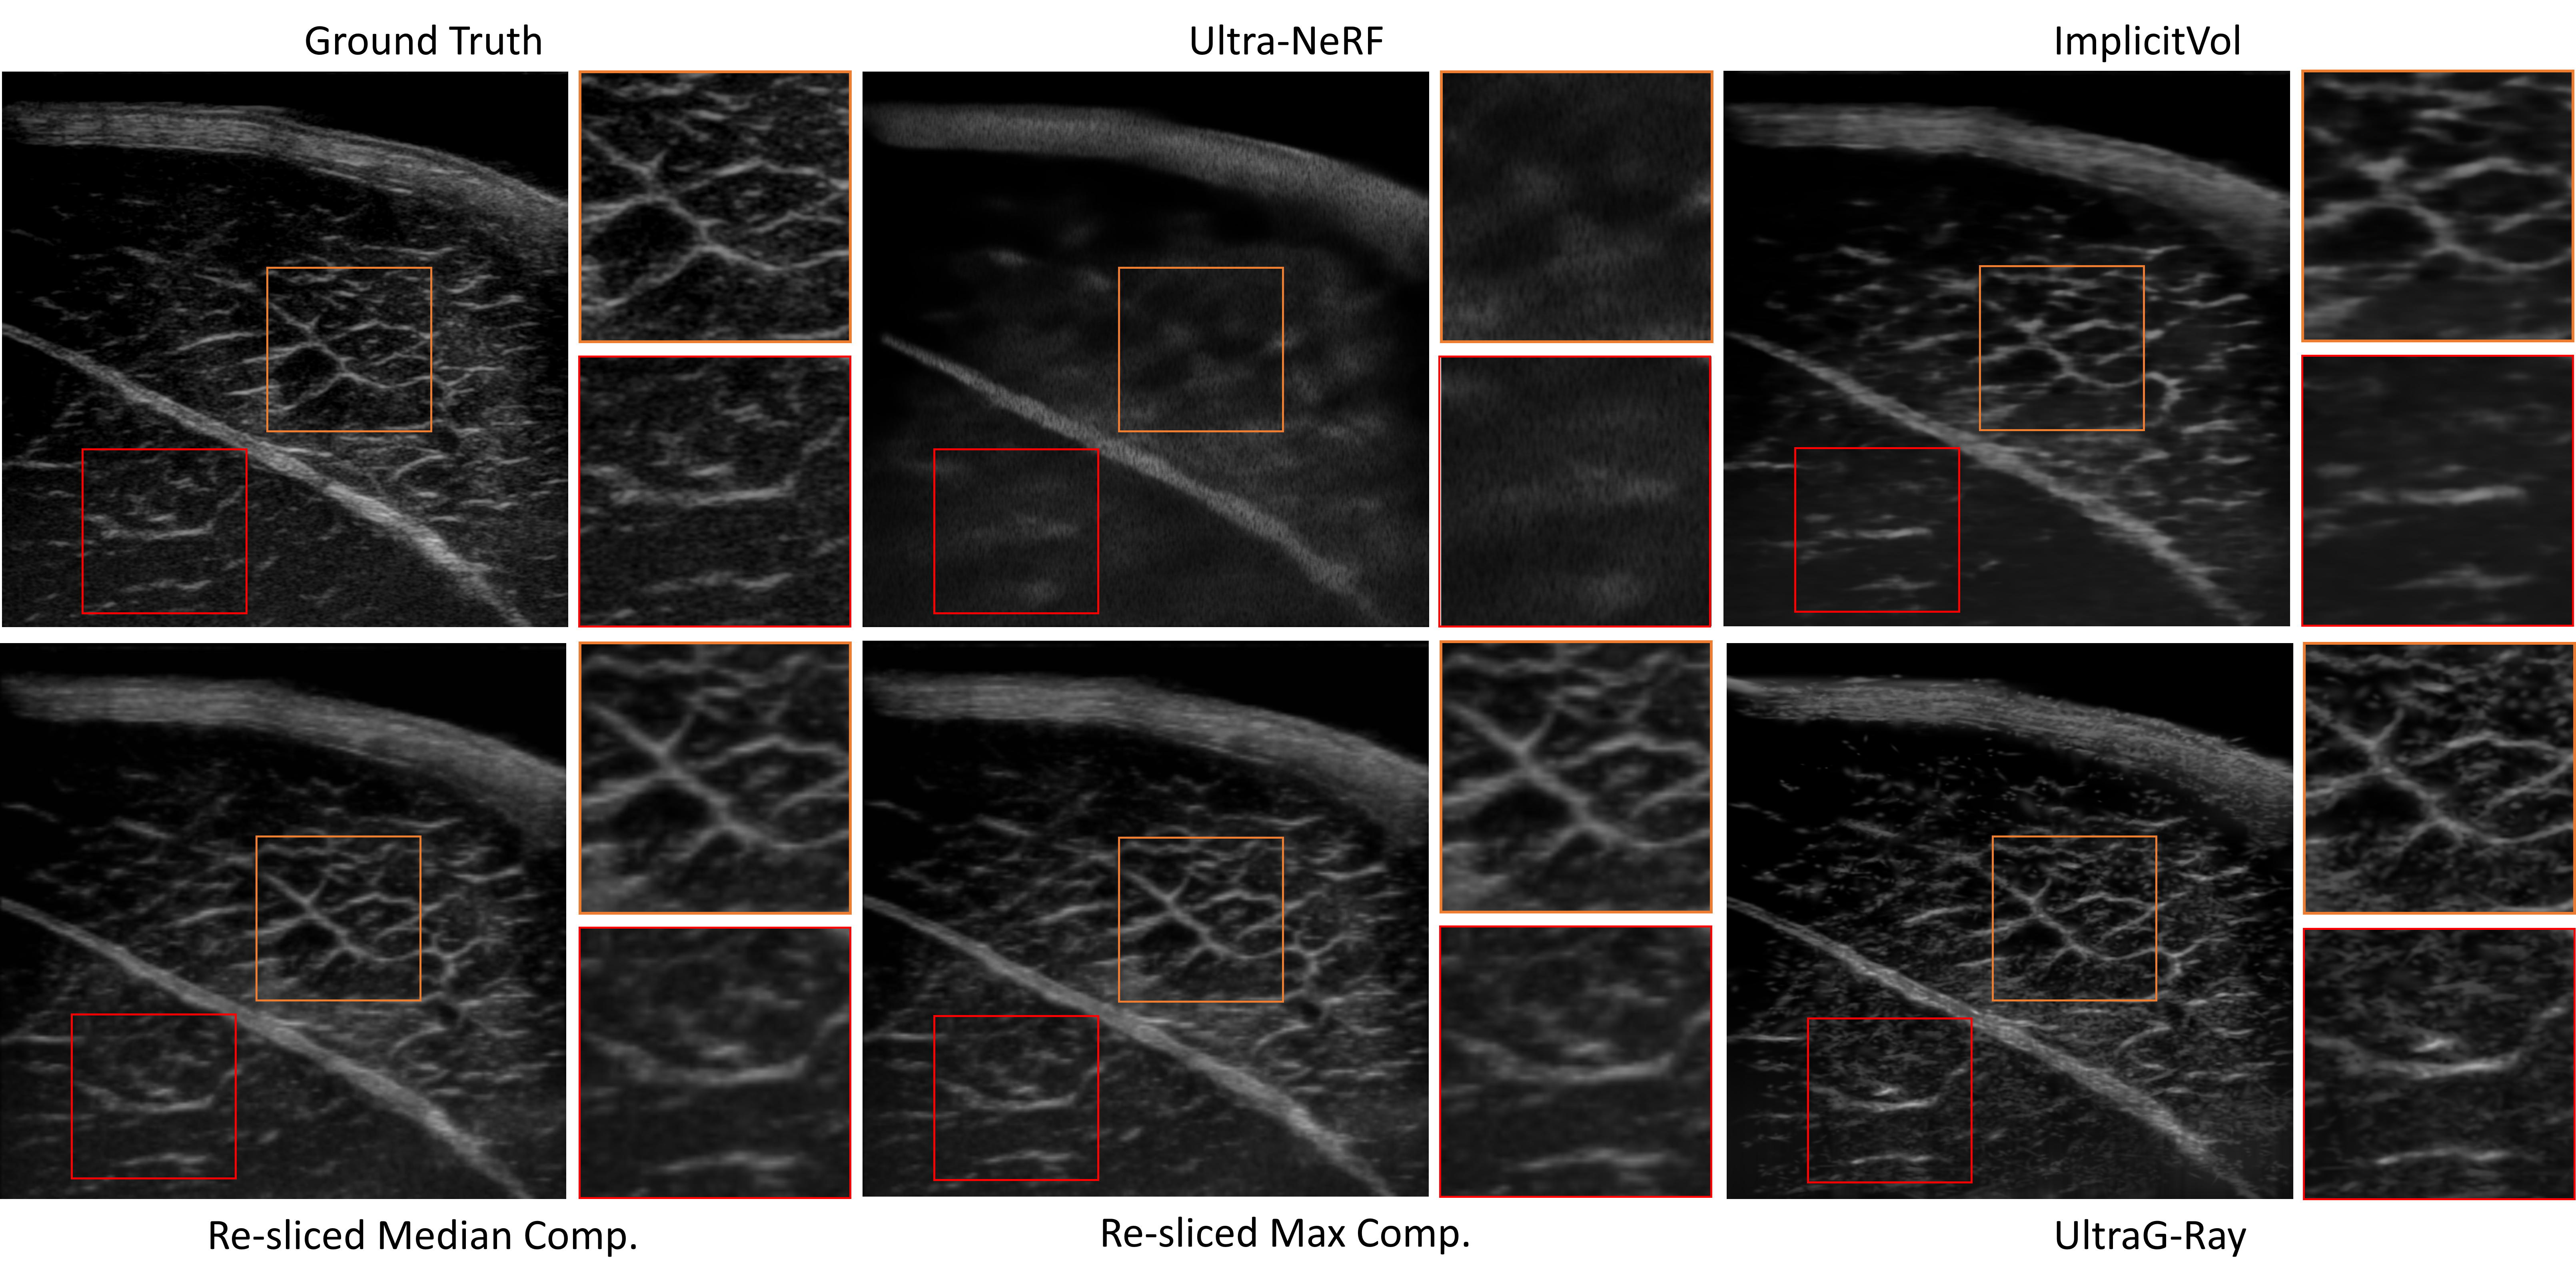

Qualitative comparison

On ex-vivo porcine muscle data, UltraG-Ray produces higher-fidelity reconstructions with clearer muscle fiber structures and improved contrast compared to prior approaches.

UltraG-Ray qualitative comparison